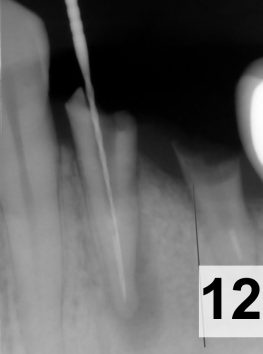

Zubní implantát je titanový „šroub“ se speciálně upraveným povrchem , který nahrazuje kořen zubu. V případě, že v místě, kam chceme implantát použít, není dostatek okolní kosti, se speciální operační technikou „ augmentace“ přidá umělá nebo kost vlastní nebo v oboje v kombinaci. Po zahojení implantátu ( 8-12 týdnů, někdy více) se na implantát může zhotovovat korunka nebo můstek.

Augmentace kostních tkání – řízená kostní regenerace je operativní postup, kdy se do místa, kde není dostatek tvrdých tkání „přidává“ tkáň, kterou během času organismus kostními buňkami proroste a defekt zahojí. Často se musí použít membrána na uzavření defektu a podporu udržení materiálu pohromadě a tam, kde chybí i měkké tkáně, zrekonstruovat i toto místo přenosem laloku. Podrobnější informace vám lékař sdělí.